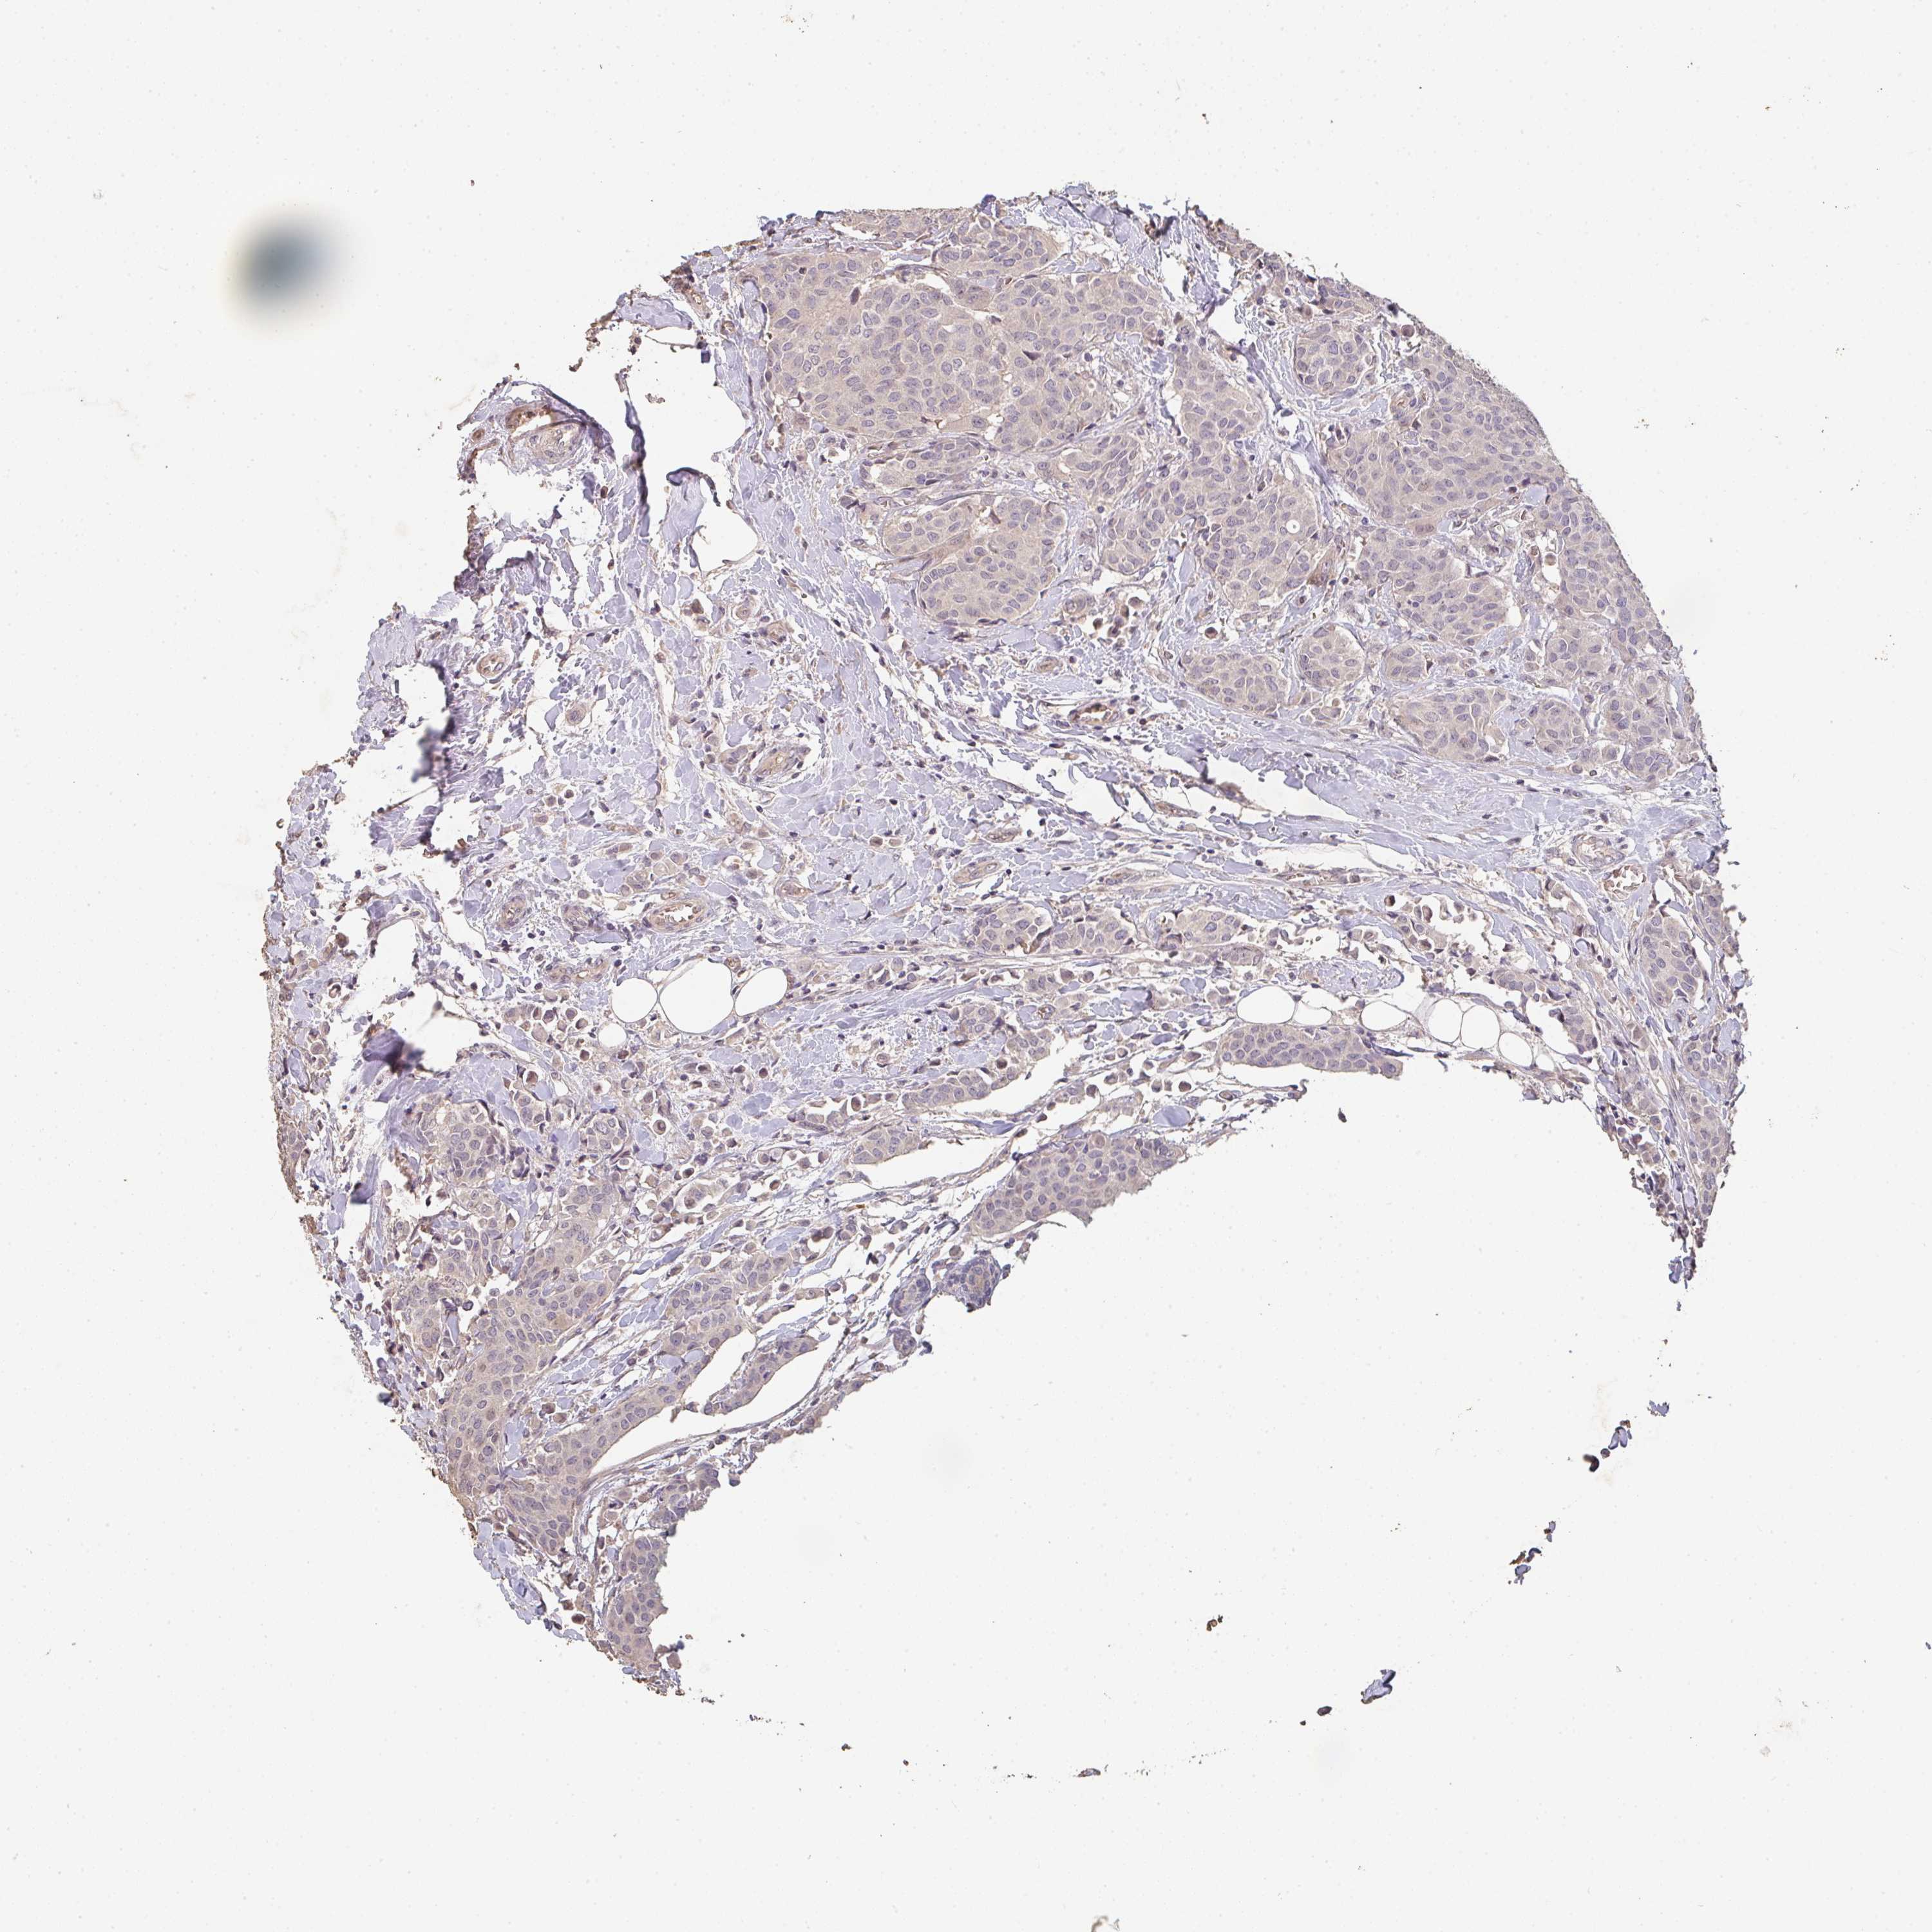

BRCA TCGA BRCA VALIDATION PROTEIN EXPRESSION